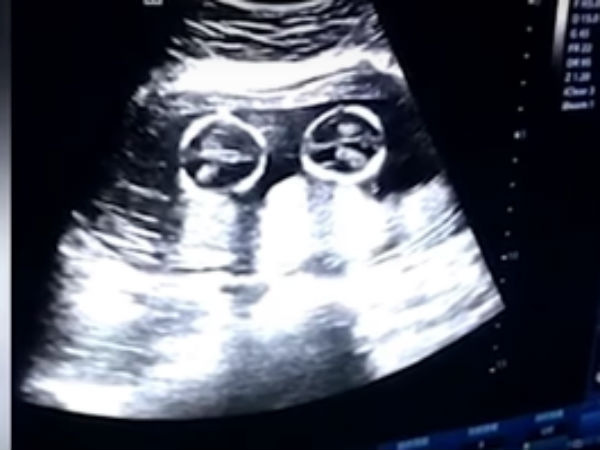

இந்நிலையில், நிறைமாத கர்ப்பிணியாக இவர் இருந்தபோது ஆஸ்பத்திரிக்கு செக்-அப்புக்காக சென்றிருக்கிறார். அங்கு அவருக்கு ஸ்கேன் செய்து பார்க்கப்பட்டது.

அப்போது கருப்பையில் இருந்த இரண்டு குந்தைகளும் சண்டை போட்டு கொண்டு விளையாடி உள்ளன. முழு கரு வளர்ந்திருந்த நிலையில் குழந்தையின் உருவம் கர்ப்பப்பையில் தெளிவாக தெரிகிறது.

குழந்தைகளின் இரு மண்டைகளும் முட்டிக் கொள்வதும், மோதிக் கொள்வதும், சில சமயம் கைகளால் தள்ளி கொள்வதும் என ஒரே சண்டையாக இருக்கிறது. இது சண்டையா, விளையாட்டா, அல்லது விளையாட்டுக்கு சண்டையா என தெரியவில்லை. இதை பார்த்ததும் குழந்தைகளின் பெற்றோருக்கு சந்தோஷம் தாங்கவில்லை.

ஆனால் இது வெறும் சண்டை மட்டும் இல்லங்க, ஒருமுறை ஸ்கேன் பார்க்க போனது ஒரு குட்டியின் தலையை இன்னொரு குட்டி அரவணைத்து இருந்த காட்சியையும் அதன் தந்தை கண்டுள்ளார். இந்த குட்டிப் பருவத்திலேயே இவர்கள் இப்படி பாசப் பிணைப்புடன் இருப்பதால் வளர்ந்த பின்னரும் இவர்கள் இணை பிரியா சகோதரிகளாக வளர்வார்கள் என்றும் அந்த தந்தை நெகிழ்ச்சியுடன் கூறுகிறார்.